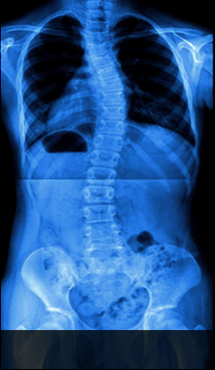

척추측만증이란?

정상

척추측만증

건강한 척추는 정면에서 보았을 때 일자로 반듯하지만, 척추측만증은 C자형 또는 S자형으로 척추가 휘어져 있습니다.

이처럼 척추의 만곡이 소실되어 척추가 왼쪽 혹은 오른쪽으로 휘어지는 증상을 척추측만증이라고 합니다.